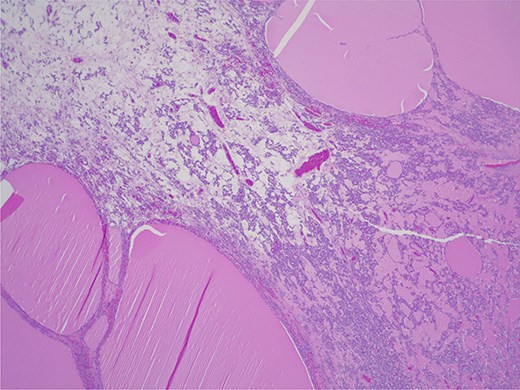

The thyroid tissue is the dominant component, along with a cyst with sebaceous material and hair.

Final histopathological examination confirmed the diagnosis of struma ovarii. On gross examination, the tumor was composed predominantly of thyroid tissue and contained a cyst filled with sebaceous material and hair (Fig. 3). The cut surface of the ovarian mass was partly solid and partly cystic, with a gelatinous, pale-yellow, goiter-like appearance (Fig. 4). Microscopically, the lesion demonstrated thyroid follicles of varying sizes filled with colloid (Figs 5 and 6), with no evidence of malignant transformation. The patient recovered well and has remained asymptomatic under regular follow-up. At 3 years post-surgery, she shows no evidence of disease.

Struma ovarii—thyroid tissue is the dominant component with large and small colloid-containing follicles: H&E ×25.